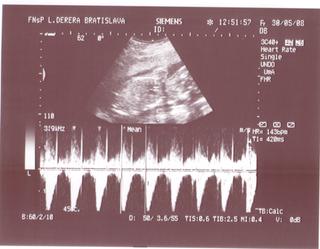

@bv_alexandra 3Dčko je skôr pre potešenie, morfologický UV je na diagnostiku, vidno na ňom orgány a kosti bábätka, vidno chlopne srdiečka, je možné zmerať dĺžku kostí a tak podobne, len pre porovnanie, už som to sem dávala aj predtým a písala som o tom, pridávam ti fotky z môjho prvého tehu, tie "farebné" sú z 3Dčka tam je krásne vidieť bábätko, tváričku, črty tváre, je vidieť na koho sa podobá, ako vyzerá, na morfologickom, to je ten čiernobiely vidieť bábo "zvnútra" aby sa potvrdilo že je úplne zdravé a nemá žiadne vývojové vady, podľa dĺžky kostí ti tam aj spresnia termín pôrodu.